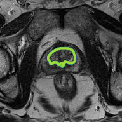

Despite their outstanding accuracy, semi-supervised segmentation methods based on deep neural networks can still yield predictions that are considered anatomically impossible by clinicians, for instance, containing holes or disconnected regions. To solve this problem, we present a Context-aware Virtual Adversarial Training (CaVAT) method for generating anatomically plausible segmentation. Unlike approaches focusing solely on accuracy, our method also considers complex topological constraints like connectivity which cannot be easily modeled in a differentiable loss function. We use adversarial training to generate examples violating the constraints, so the network can learn to avoid making such incorrect predictions on new examples, and employ the Reinforce algorithm to handle non-differentiable segmentation constraints. The proposed method offers a generic and efficient way to add any constraint on top of any segmentation network. Experiments on two clinically-relevant datasets show our method to produce segmentations that are both accurate and anatomically-plausible in terms of region connectivity.